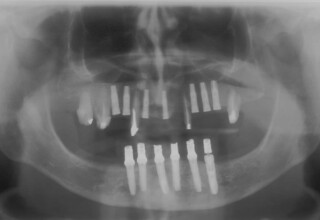

Κάτω γνάθος: εξαγωγές, άμεση τοποθέτηση εμφυτευμάτων και άμεση φόρτιση(την ίδια ημέρα) με προσωρινή γέφυρα

Άνω γνάθος: σταδιακές εξαγωγές, σταδιακή τοποθέτηση εμφυτευμάτων και σταδιακή ενσωμάτωση τους στην προσωρινή γέφυρα ώστε η ασθενής να μην μείνει ούτε μια ημέρα χωρίς αποκατάσταση. Στόχος η συνεχής λειτουργική και αισθητική αποκατάσταση της ασθενούς χωρίς άμεση φόρτιση των εμφυτευμάτων λόγω ανατομικών ιδιαιτεροτήτων.

Χρησιμοποιήθηκαν παλαιές χαμογελαστές φωτογραφίες της ασθενούς γιατί είχε χαθεί τελείως το φυσικό σχήμα των δοντιών εξαιτίας των πολλαπλών προσθετικών προσπαθειών που είχαν γίνει στο παρελθόν. Μεταφέρθηκε στην προσωρινή γέφυρα η σχέση των φυσικών δοντιών μεταξύ τους άλλα και με τα χείλη. Δοκιμάστηκε η φώνηση και η μάσηση με δυο διαφορετικές προσωρινές άνω γέφυρες και εκτιμήθηκε η αισθητική απόδοση τους. Αφού επιτεύχθηκαν σε βαθμό ικανοποιητικό η φώνηση και η αισθητική εμφάνιση της οδοντοφυΐας, η προσωρινή αποκατάσταση χρησιμοποιήθηκε ως οδηγός για την τελική.